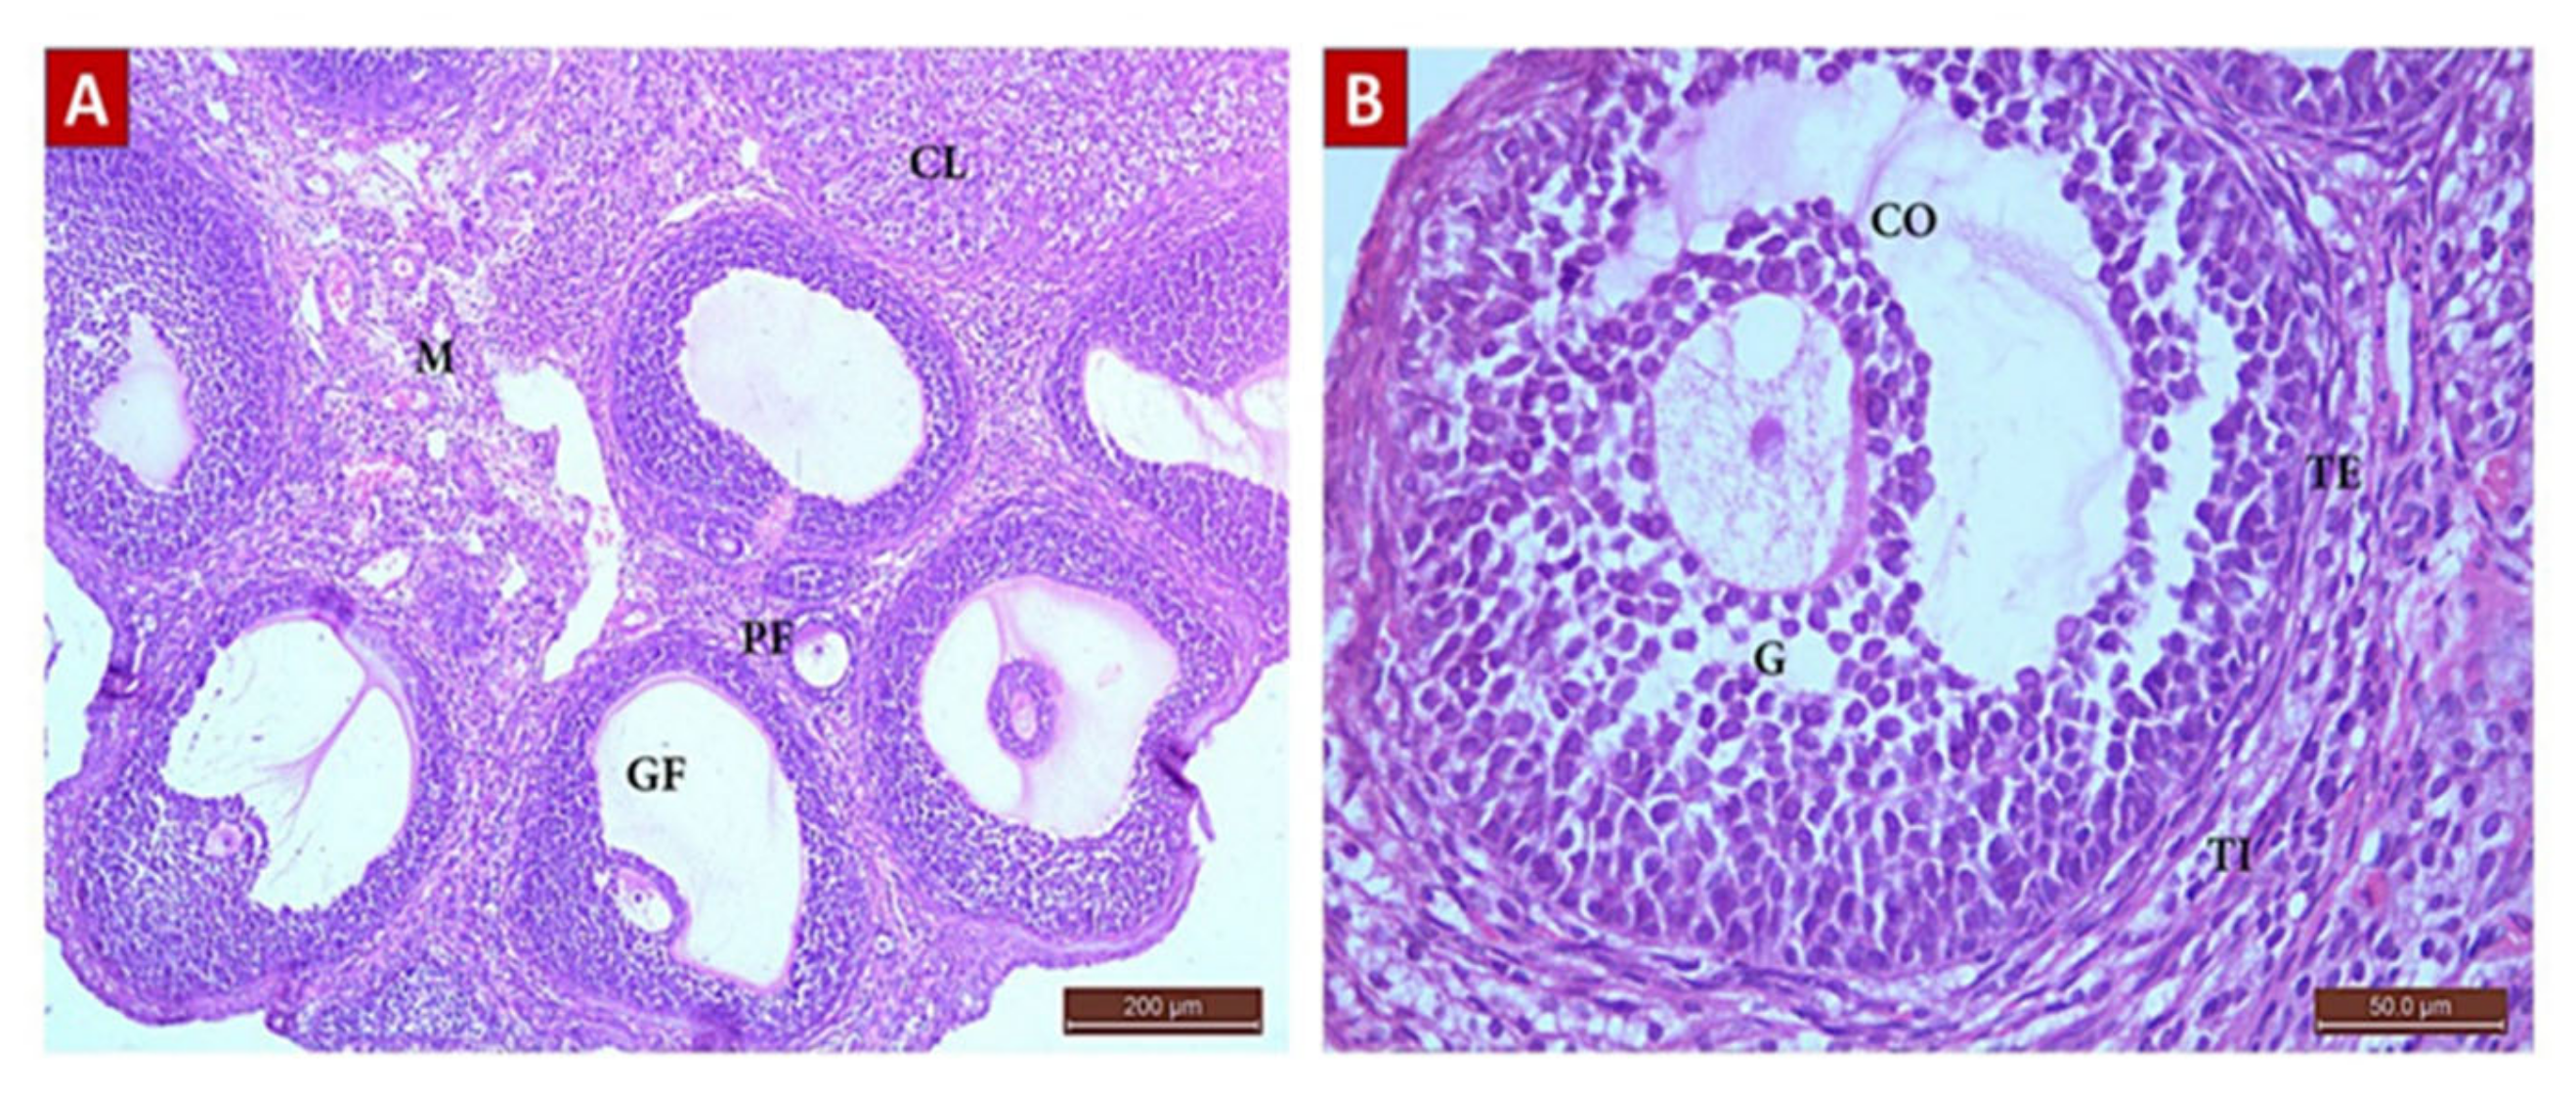

The Control Group (Group I, Figure 1, Figure 2, Figure 3 and Figure 4)